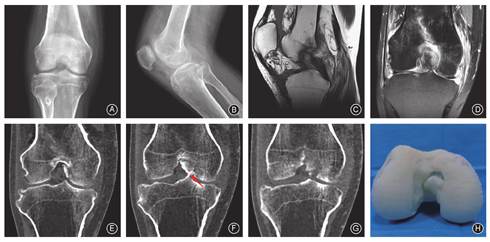

体格检查:拄拐跛行;右膝关节轻度肿胀,皮温正常,浮髌试验(+);Lachman试验(-)、前抽屉试验(-)、反Lachman试验(+)、后抽屉试验(+)、麦氏征(-)、Apley试验(-);右膝关节伸直-20°,屈曲120°;额面部皮肤局部稍隆起、触之弹性减低,双手杵状指、双足足趾畸形、足趾掌和(或)跖侧皮肤角质化(图1)。实验室检查:2020年至2023年规律血常规、肝功能、肾功能、电解质及骨代谢指标检查,仅骨折后3周的随访β-CTX升高至0.621 ng/ml(参考范围0.112~0.497 ng/ml),其他指标均处于正常范围。影像学检查:伤后X线片示髁间窝有骨性结构占位,疑似骨折块;CT示股骨内髁外侧壁后十字韧带股骨止点处撕脱骨块且向髁间窝内移位;MRI示后十字韧带股骨附着点撕脱骨折(图2)。

术后X线、CT扫描及三维重建示骨折解剖复位且维持良好(图4)。术后3个月随访时患者膝关节运动范围为0°-120°、Lysholm功能评分89分,可正常行走,但无法从事高强度体育锻炼。厚皮性骨膜病病情平稳,无明显进展。